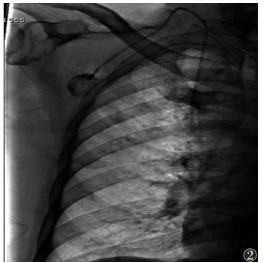

1.2 仪器与方法采用巴德5F植入式静脉输液港、穿刺套件、心电监护仪、蝶翼针。由2位具有5~10年植入经验的医师与1位护士在DSA引导下采用2种不同的穿刺入路植入输液港,术中行X线检查确保导管位置并判断有无血气胸等并发症。①锁骨下静脉入路:于锁骨下约1 cm、中外1/3交界处穿刺,在导丝引导下引入输液港,将导管末端置于上腔静脉和右心房交界处(约T6~T7椎体水平),经DSA确认后建立囊袋(锁骨下窝处)以放置港体、打通皮下隧道,连接固定港体与导管(图 1)。②颈内静脉入路:于颈内动脉偏外约0.5 cm、斜角肌三角顶点处穿刺,在导丝引导下引入导管(导管末端位置同上);建立囊袋、打通皮下隧道,连接导管与港体,注意翻转导管经皮下隧道下行至锁骨下窝处(港体埋植处)(图 2)。操作时若误入动脉,须立即停止并加压止血10 min;若出现气胸须暂停手术,并观察5~10 min,若大量气胸须行胸腔穿刺引流。

| 图 2 经颈内静脉穿刺入路植入输液港 |